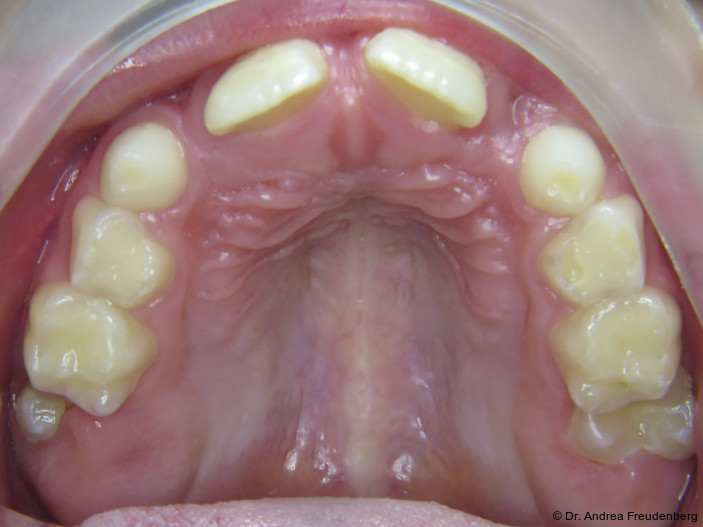

Da Pathologie, d.h. Fehlwachstum, allgegenwärtig ist, möchten wir kurz die physiologische Gebissentwicklung ins Gedächtnis zurückrufen. Ein physiologisches Milchgebiss sollte

- eine halbrunde Form der Zahnbögen,

- eine dezente sagittale und vertikale Frontzahnstufe und

- im Alter von vier bis fünf Jahren Lücken zwischen den Milchschneidezähnen aufweisen (die bleibenden Frontzähne sind ca. ein Drittel breiter als die Milchzähne).